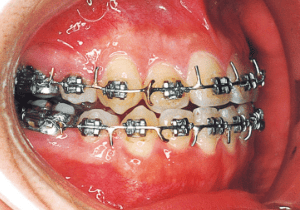

6

The Edgewise appliance was applied locally (8) and removed after 11 months (9). However, as the maxillary molar region gradually became crossbite, the maxillary arch was laterally expanded using a quad helix.

Although early treatment improved the slight deviation observed during the deciduous dentition stage, it became apparent that the deviation increased with age, eventually exceeding the limits of treatment. This appears to be an innate deviation, and the developmental pattern observed in this case seems to disregard the occlusion. Four first premolars were extracted (15), crowding was corrected and space closure was performed (16), and surgical intervention improved the deviation (17).